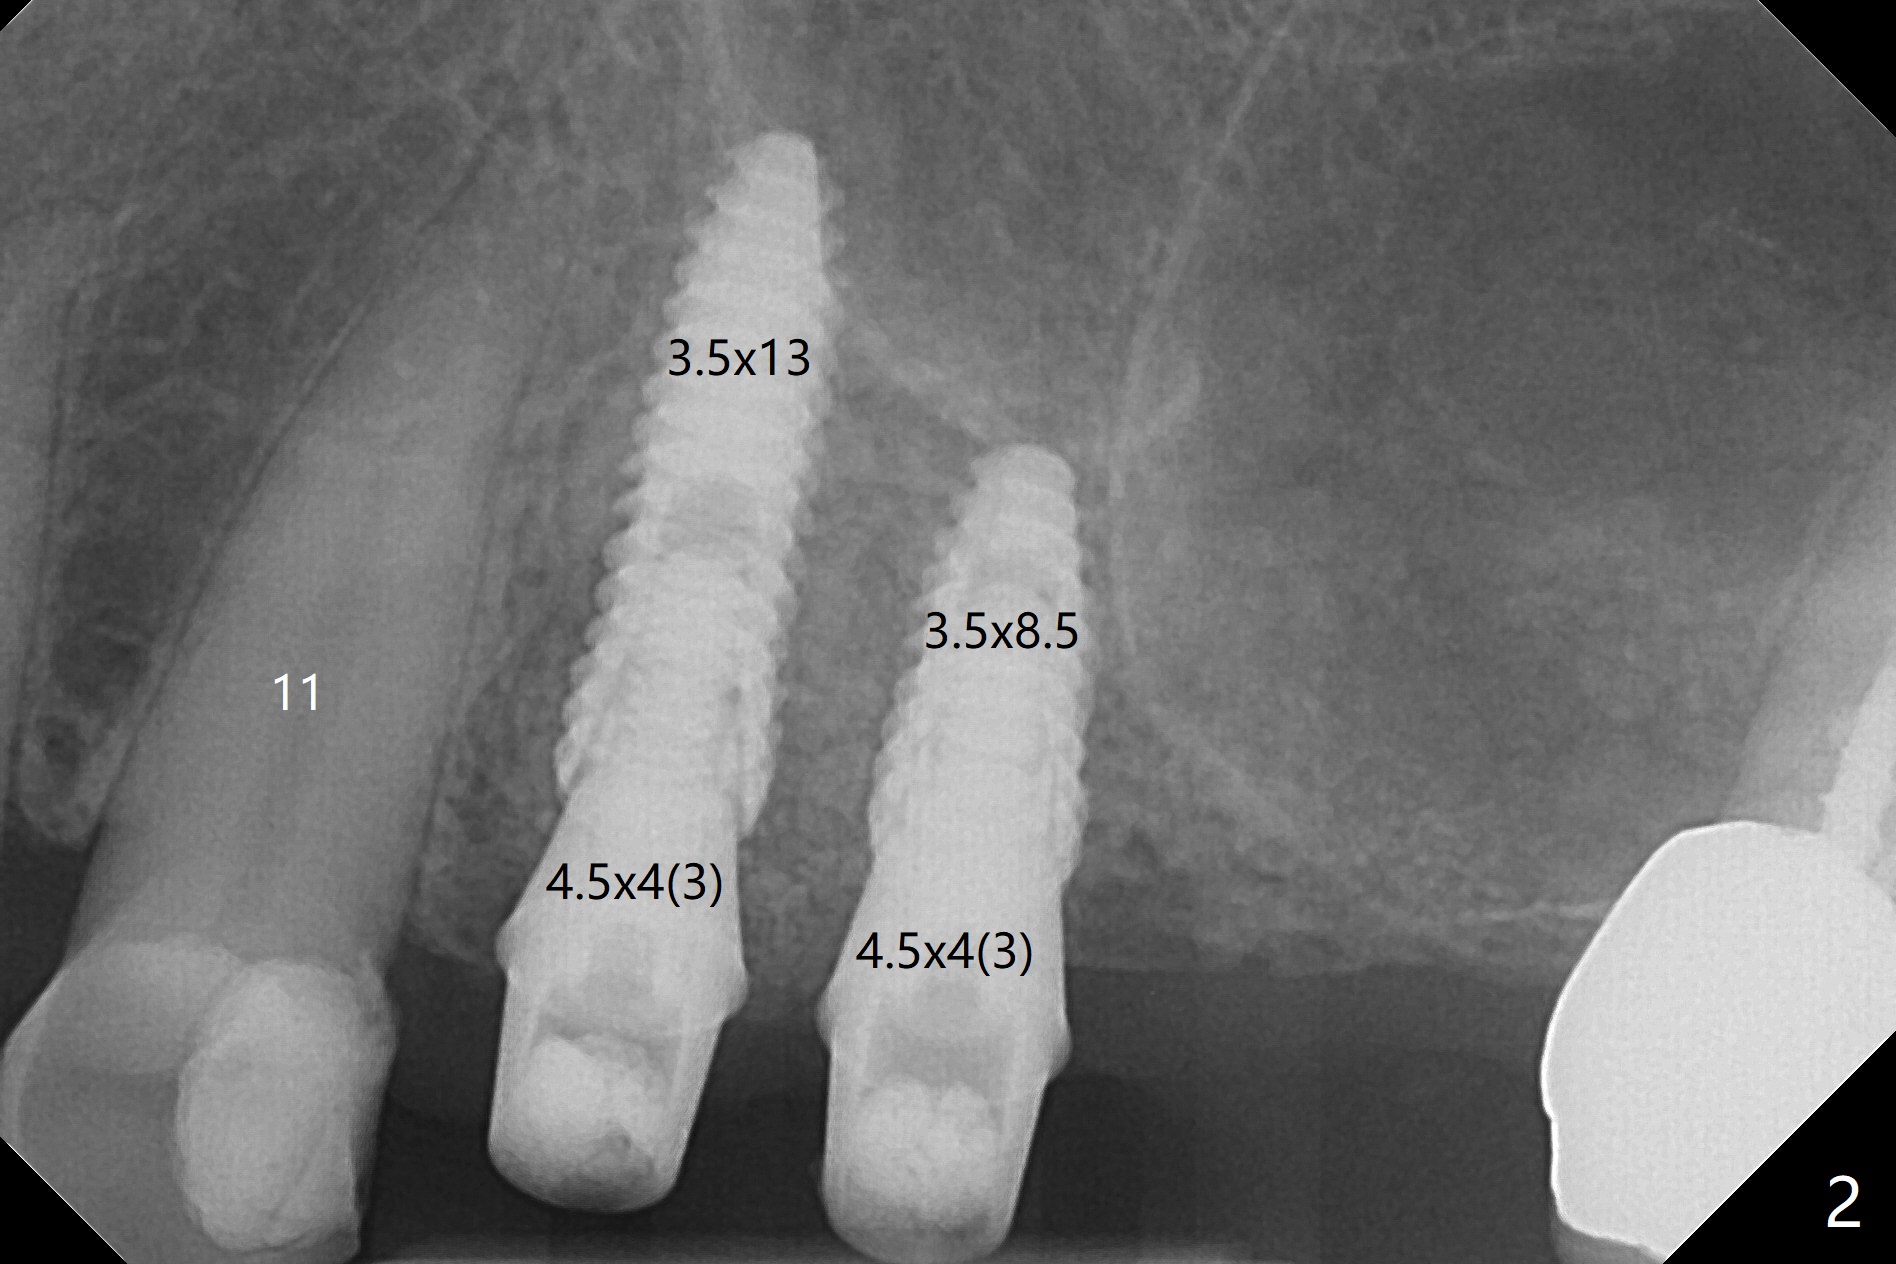

Osteotomy at #3 is performed last (Fig.1,2); as planned, a 4 mm cortical tap is used with guide for sinus lift. Unfortunately the sinus membrane is perforated. Implant placement is aborted. Instead Osteogen plug is inserted into the osteotomy, which is fixed in place by acrylic extending from the provisional at #4. Osteotomy for #3 implant will be attempted with control of the depth in 4 months. The patient has allergy to Amoxicillin (rash). When switching to Clindamycin, she develops diarrhea and loses 10 pounds. There is no abnormality at the site of #3 or 4 nearly 3 months postop (Fig.3). The next surgery will be most likely conducted without antibiotic 4 months postop. Try to draw blood for PRF. Take PA for #12 and 13 for possible impression. Remove the 3 temporary crowns, seat the guide across the arch and use no-stop fixture mounts at #4, and possibly 12 and 13. Follow the original drill sequence (check perforation after each drill, Fig.11) and use DIONavi sinus approach kit. Also load an appropriate stop for the round bur for sinus lift before hand. Mixture allograft with Metronidazole and PRF. In fact everything goes on as smoothly as planned. Osteotomy at #3 is underprep (3.5 mm in diameter drill instead of 4.0). The sinus floor appears to remain to be absent; 3.2 mm round bur is used for lift, alternating with water pumping. Following insertion of 3 pieces of PRF membranes and Vanilla Graft (Fig.4 *), a 4x10 mm dummy implant is placed. After additional bone graft (Fig.5 *), a final 4.5x7.3 mm implant is placed ~10 Ncm. The implant is placed deeper ~ 1 mm, followed by a 5.5x3 mm healing abutment (Fig.6). The implants at #12 and 13 seem to have osteointegrated (Fig.7). Impression is taken for #4, 12 and 13 with limited vertical space (Fig.8,9). An implant at #14 is being considered. There is faint bone graft around the apex of the implant 4 months postop (Fig.10). The implant sustains 25-30 Ncm torque when a 5.2x4(3) mm cemented abutment is placed. A permanent crown is cemented nearly 5 months postop (Fig.11). For the best cosmetic and masticating results, the occlusal surface should have certain degree of morphology, such as the buccal cusps (Fig.12 white curved lines). The abutment at #3 is placed and torqued to 30 Ncm before re-cementation of the repaired crown (increased occlusal surface contact). In fact the abutment at #4 is incompletely seated with a gap (Fig.13 <). The composite at #5 is dislodged while #3 crown is being repaired (*). The abutment at #4 is loose >1 year post cementation. The abutment remains incompletely seated (gap and longer apical space (double arrows)) when the abutment/crown complex rotates lingual mesiobuccal (Fig.14 curved arrow). Further proximal reduction and lingual rotation distobuccal leads to complete seating (Fig.15). It appears that incomplete seating at #13 is associated with hex mismatch (Fig.16, large apical space), which will be fixed next visit. One week later, the crown and abutment of #4 are seated together after crown repair (Fig.17). Since the abutment margin is subgingival, the crown is cemented, removed with abutment for residual cement removal and reseated with the abutment with torque at 30 Ncm. After this, the crown and abutment of #13 is reseated after mesiobuccal surface is trimmed (Fig.18), followed by pick up impression. A few days later, the crown/abutment are inserted together smoothly, the former cemented and the complex unscrewed for residual cement removal and last torqued at 30 Ncm without any X-ray confirmation.